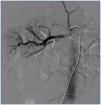

A 26-year-old man presented with a few weeks history of nausea, malaise, blurred vision, a brief episode of visual loss and hypertension. While working, he experienced loss of sight but regained it after a couple of minutes. He had no history of chronical disease. Family history of patient was not contributory-without a family history of vascular disease or hypertension. He was not taking any medications and denied any heavy alcohol, cocaine or intravenous drugs use, but had a 10-pack-year tobacco history. On review of systems, he reported 6-7 kilograms of unintentional weight loss in the past one year. Blood pressure was 150/70mm/Hg, a temperature of 36.8oC, heart rate of 64/min, and respiratory rate of 16/min. Cardiovascular and respiratory system examination was not remarkable. Indirect ophthalmoscopy was performed; retinal detachment (exudative) in both eyes, raised papilla limits, retinal vessel tortuosity, choroidal hypopigmented lesions under retina and superficial haemorrhages were detected. Exudative retinal findings defined as Vogt-Koyanagi-Harada syndrome. Laboratory and ultrasonographic findings were shown at Table 1. Peripheral blood smear revealed; enough platelets with normal morphology, schistocytes were rare, reticulocytes <2%, normochromic normocytic red blood cells. Primary hematological disease was not considered. He was started to be investigated for primary hyperaldosteronism, Cushing's disease and pheochromocytoma. During the follow up in nephrology service, the patient had presyncope, convulsion, hypertensive emergency and altered mental function. His blood pressure was 220/110mm/Hg. Blood pressure was controlled via sodium nitroprusside infusion for 48 hours and amlodipine 10mg, nebivolol 5mg, doxazosin mesylate 8mg at following days in intensive care unit. After the neurology consultation was performed the patient was evaluated with magnetic resonance imaging (MRI). Bulbus, pons and left mesencephalon, basal ganglia, peri-supraventricular white matter areas of increased T2 signal is considered to be consistent with vasogenic edema. Subretinal haemorrhages were detected at posterior parts of both orbit. It was reported as posterior reversible encephalopathy syndrome (Figure 1). After 5 days of intensive care follow up the patient had normal blood pressure. After excluding frequently seen secondary hypertension causes, renal and mesenteric angiography was performed at the same time suspecting renovascular hypertension. Angiography revealed multiple microaneurysms involving the parenchymal branches of the celiac artery, bilateral renal artery and superior mesenteric artery (Figure 2 and Figure 3). After the angiography, eventually, ultrasound-guided renal biopsy was performed. Light microscopy revealed 9 glomeruli with no specific patterns except a slight increase in mesangial matrix. Normal interstisium, tubular focal atrophy and intimal-medial thickening of blood vessels was apparent. Due to increased cellularity obstruction and perivascular fibrosis were found in blood vessels. Histochemically, periodic acid-Schiff, M. Silver, Masson’s Trichrome staining was used. Congo red staining was negative. With direct immunofluorescence method, there was no specific deposition of IgA, IgG, IgM, C3, C4, C1q, fibrinogen, kappa and lambda. Histological diagnosis was reported as signs of vascular myointimal hyperplasia (Figure 4). With all these findings (clinical characteristics such as severe hypertension and renal insuficiency, constitutional symptoms such as malaise and weight loss, inflammatory parameters like elevated erythrocyte sedimentation rate-ESR and C-reactive protein-CRP, angiographic findings) the patient was diagnosed as PAN. Oral prednisolone therapy as 0.5mg/kg/day had been given. But as creatinine levels raised up and hypertension could not be well controlled with drug therapies, eventually hemodialysis was started (Figure 5).

Figure 2. Multiple microaneurysms involving the parenchymal branches of the celiac artery, bilateral renal artery and superior mesenteric artery

Figure 3. Multiple microaneurysms involving the parenchymal branches of the celiac artery, bilateral renal artery and superior mesenteric artery